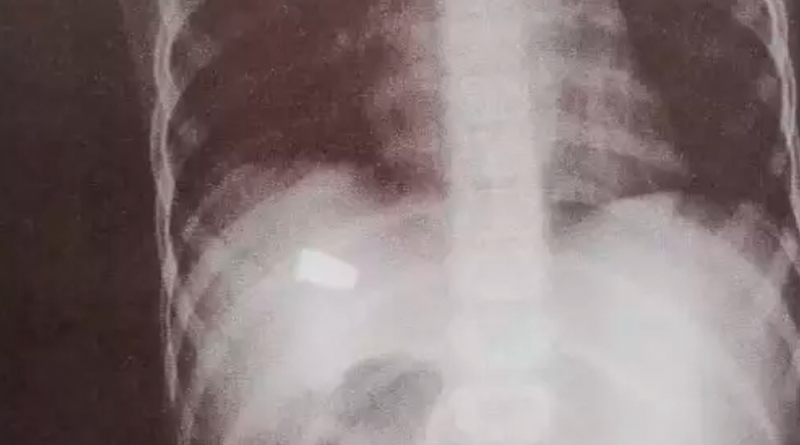

O menino disse à madrinha que sentiu dor no abdômen após ser atingido por um pedaço de telha da casa. Ao fazer um Raio X, foi constatado que a criança foi atingida por um tiro.

Na UPA, após realizar um exame de raio-x, os médicos identificaram que a lesão foi causada por um disparo de arma de fogo.